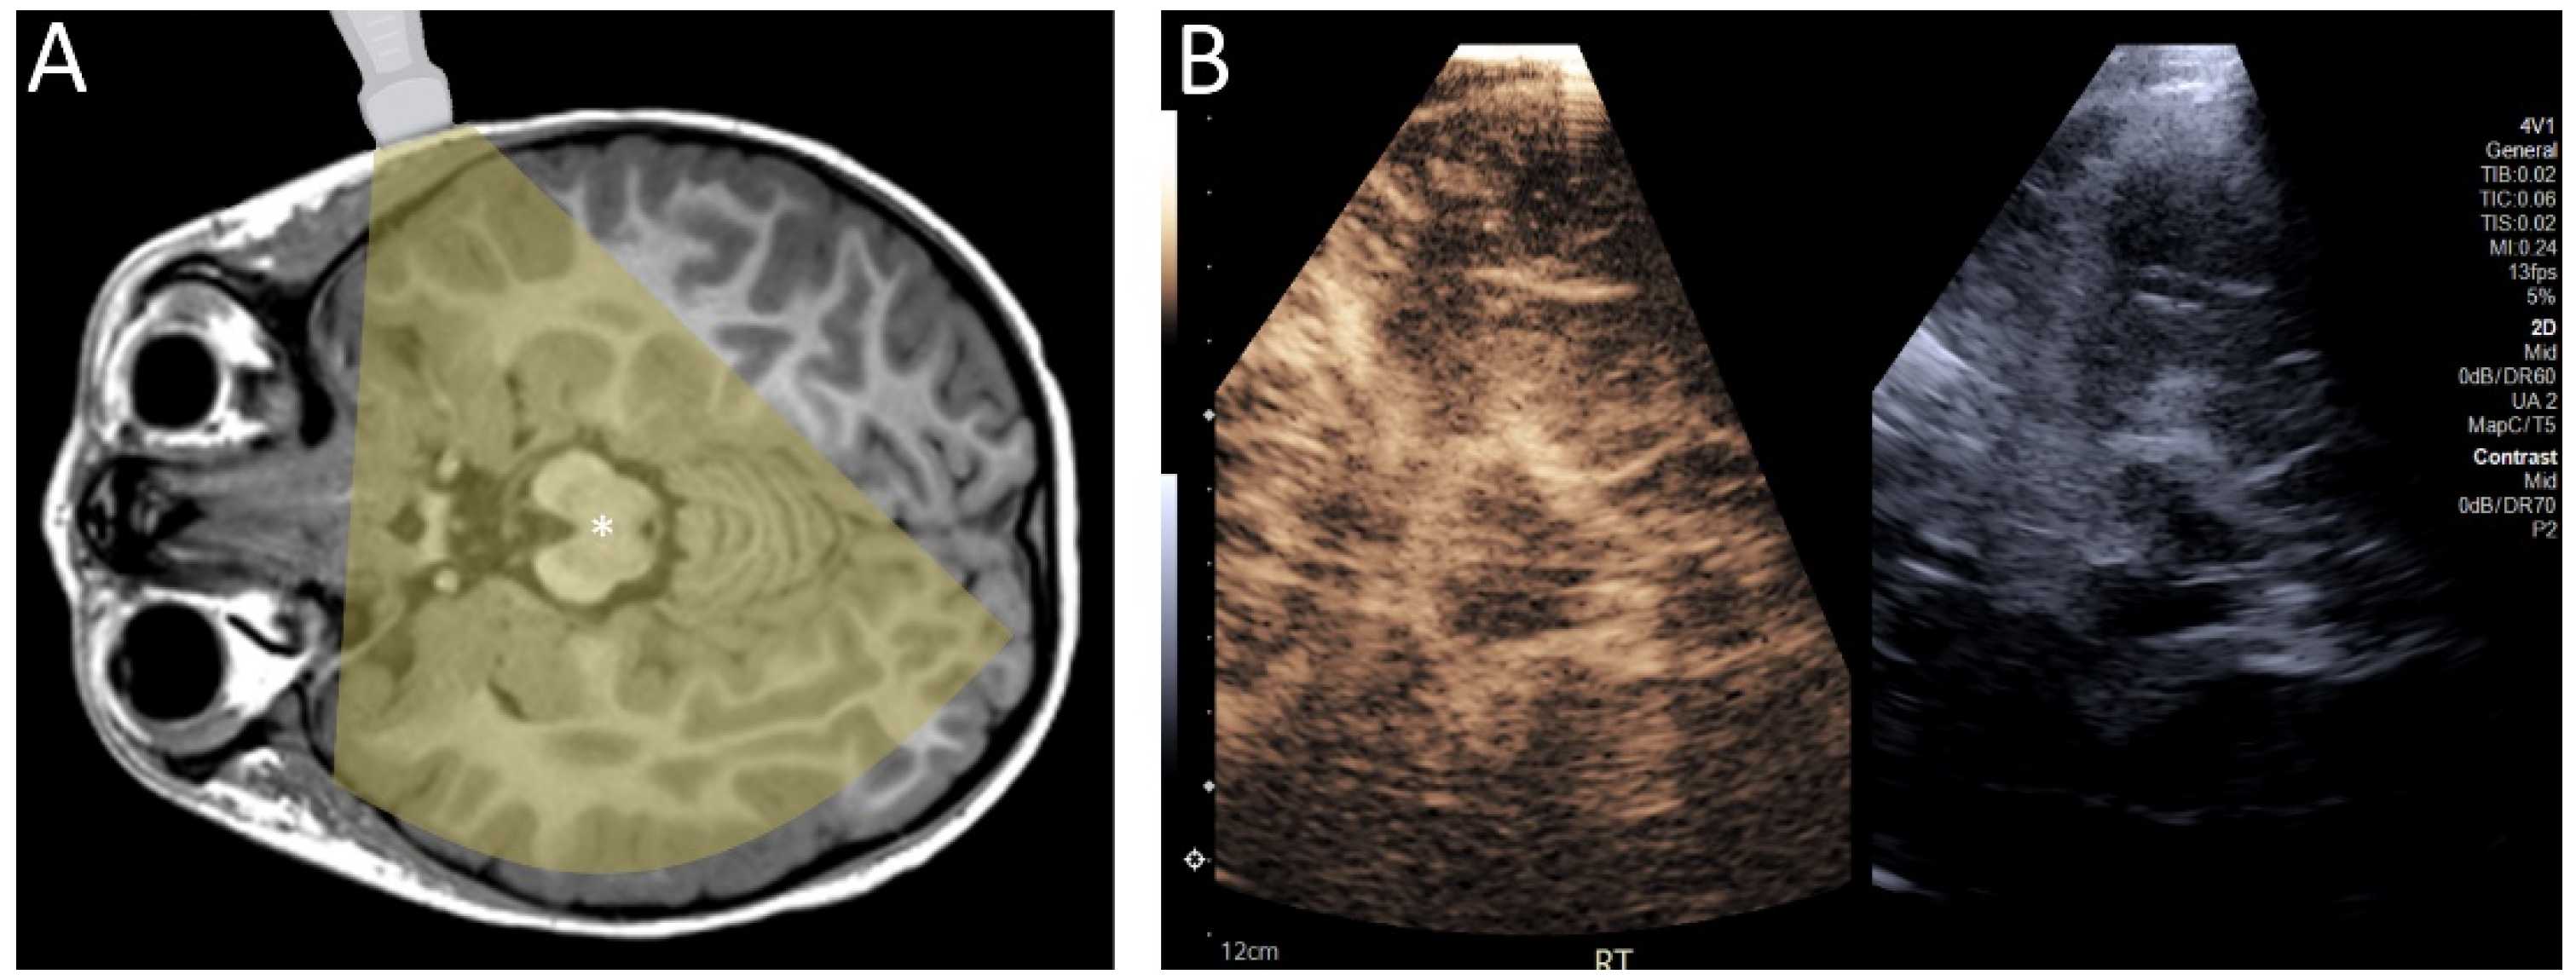

Figure 4.

(A) Diagram demonstrating the transtemporal approach for ultrasound. (B) Contrast-enhanced ultrasound of the brain of a 4 year old child through a transtemporal window. In infants, ultrasound can be performed through open fontanelles. In older individuals, including children and adults, ultrasound can be performed through the transtemporal window.